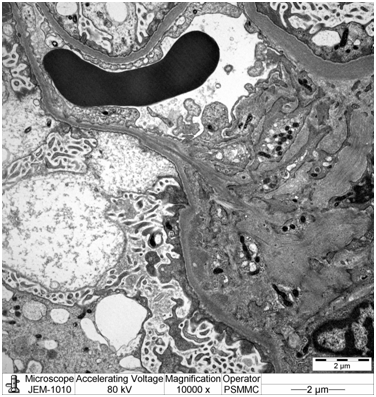

Electron microscopy: Sections stained with Toluidine blue stain showed the renal cortex containing 16 glomeruli, none globally sclerotic. Ultrastructure evaluation showed diffuse epithelial foot processes effacement with microvillus proliferation, mild amounts of electron dense deposits in the mesangial region. The glomerular basement membranes were normal thickness (Figure 2&3).

Figure 3: High power EM image showing the diffuse epithelial foot processes effacement with microvillus proliferation.

Focal segmental glomerulosclerosis is a common cause of end stage renal disease requiring renal transplantation [3]. In the pediatric age group, FSGS has a high rate of recurrence (up to 30%) [4-6]. The risk of recurrence in the first graft is high, up to 30%, with graft loss of 40-60% [4,7] while the risk of recurrence in a second graft is 60–100% [8]. Risk factors include: Onset of nephrotic syndrome during childhood, rapid course to ESRD (<3 years), female sex, bilateral nephrectomy, mesangial hypercellularity, presence of FSGS circulating factor [4,5]. The podocin mutation may play a role in pathogenesis and early recurrence of FSGS [3,9]. The presentation of recurrence includes early massive proteinuria (78% during the first month after transplant, often as early as in the first urine from the graft) and sometimes graft failure and hypertension [9]. Proteinuria may herald the development of FSGS even if an early biopsy does not show glomerular abnormalities under light microscopy (as our case). In other words light microscopy will not show any evidence for FSGS and only the presence of diffuse epithelial foot process effacement on electron microscopic examination can prove the diagnosis pathologically.